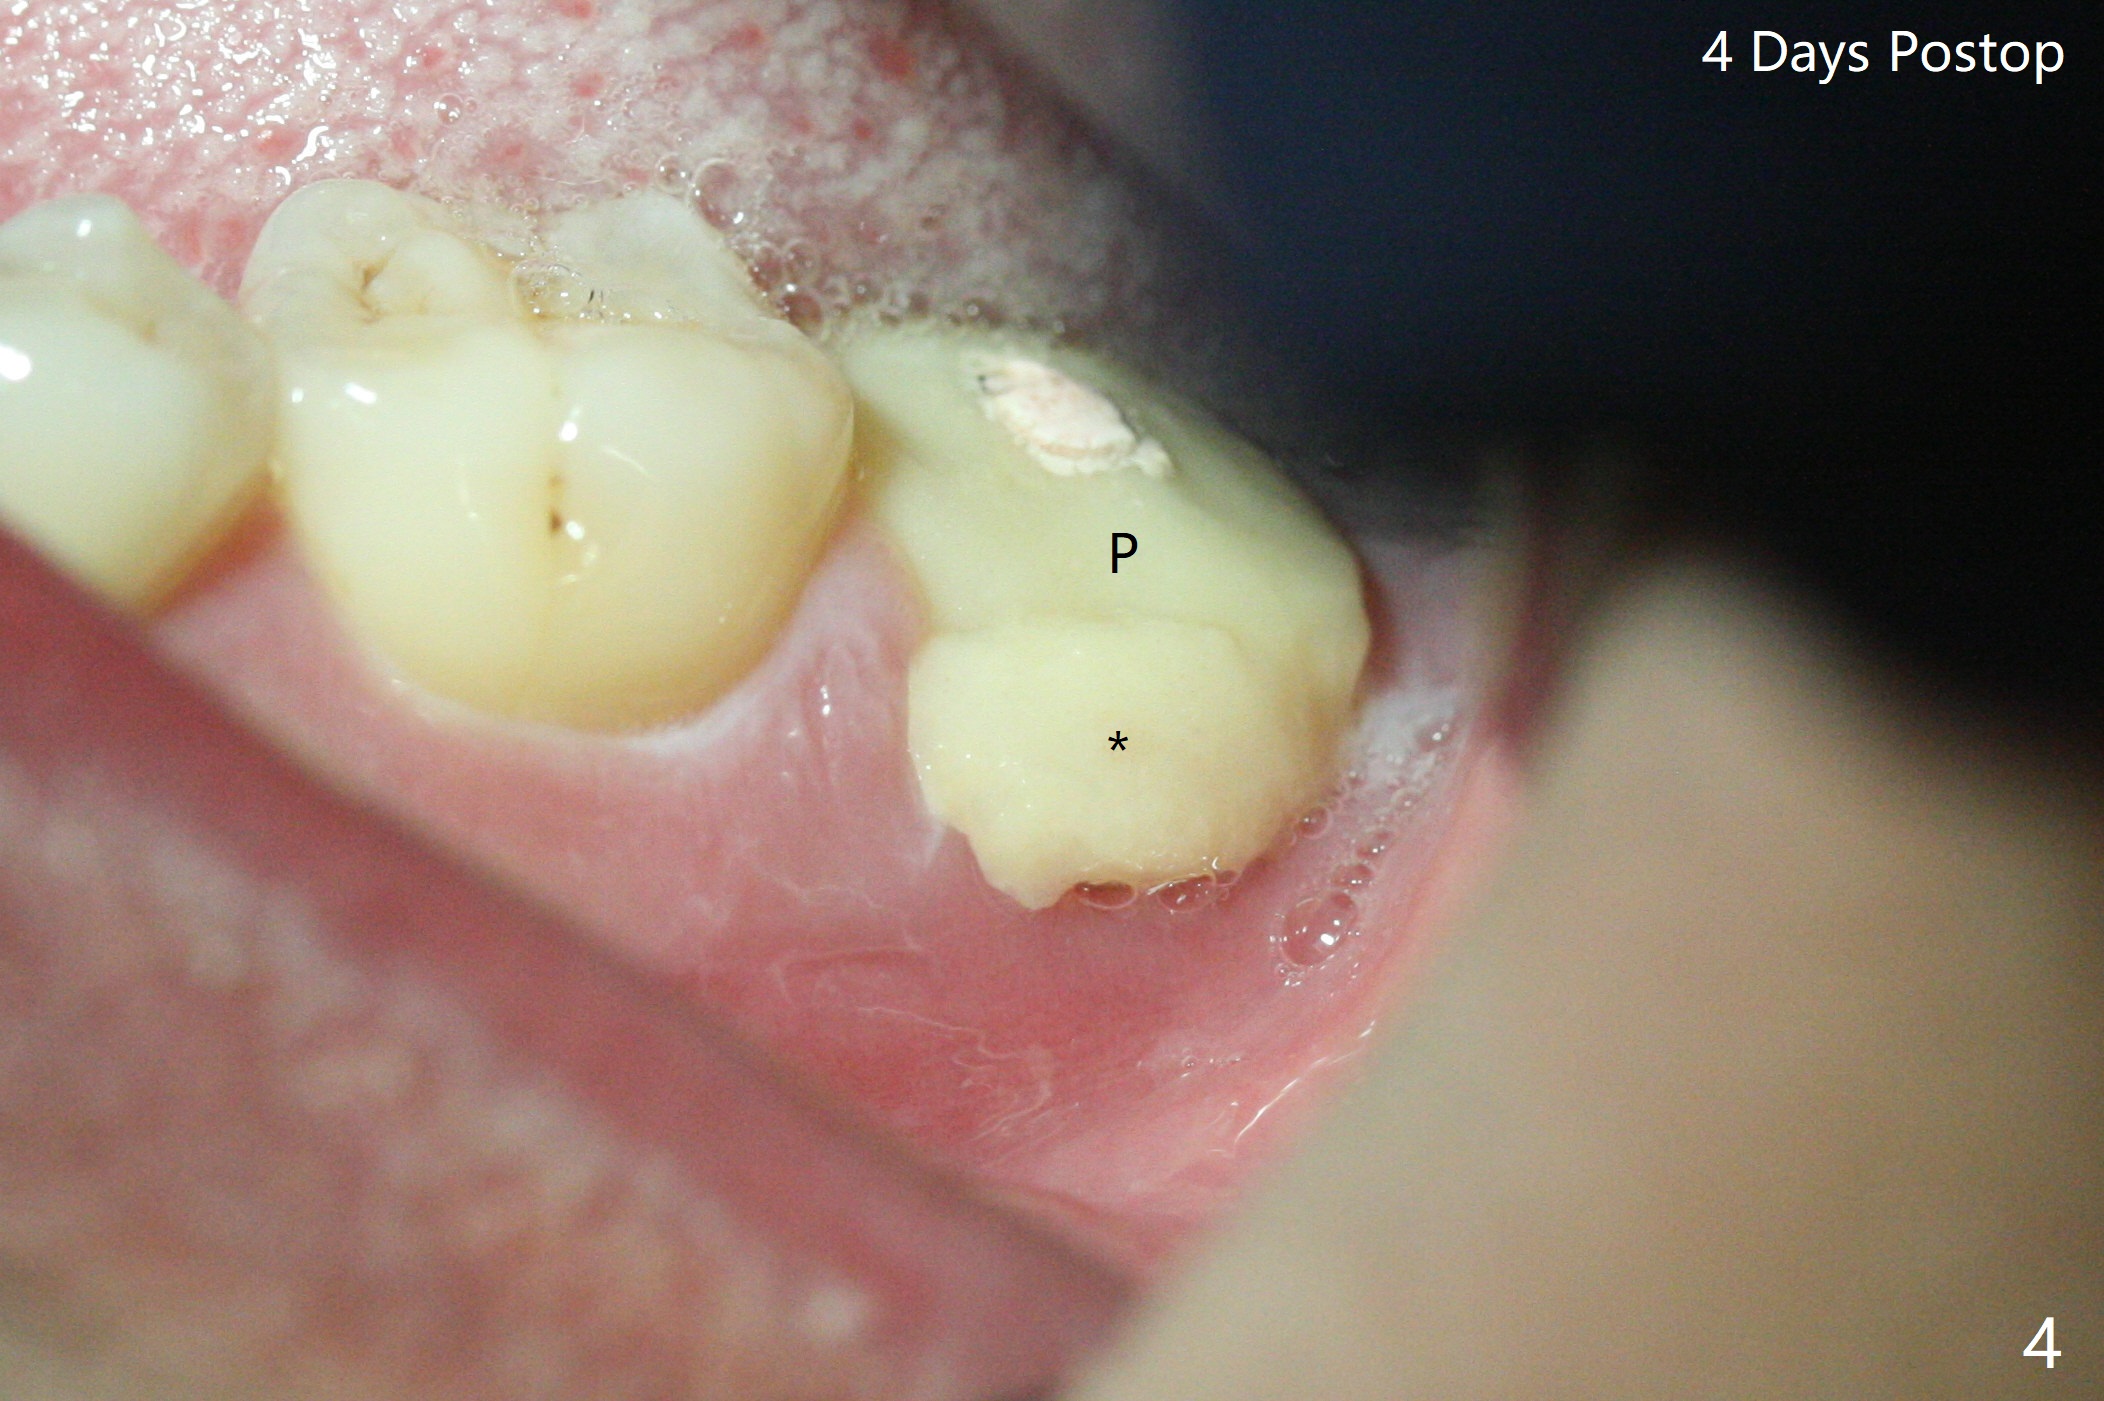

After placement of a 5x11 mm implant and cover screw at #18, allograft mixed with PRF (sticky bone) is placed in the peri-implant space, but it appears that bone density in the apical region (Fig.1 A) is lower than that in the coronal one (C) because of a constriction between the implant and the distal crest (*). Ideally the undercuts (Fig.2 *) of the extraction socket (black area) should be identified. Place bone graft in the undercuts (Fig.3 red circles) after osteotomy (white outlines) and before implant placement! A 4.5x1 mm temporary abutment is placed for an immediate provisional. The 2nd shortcoming of this case is that the implant is placed a little buccal. The papilla mesial to the immediate provisional (Fig.4 P) looks normal 4 days postop (no food impaction is expected when a final restoration is cemented). Additional acrylic (*) was placed to close a buccal gap when the provisional was seated with the temporary abutment. The patient reports loss of a piece of material in 4 days. It must be the additional acrylic, since it is absent 6 weeks postop (Fig.5). The provisional (Fig.5 P) looks wide, probably related to post-extraction gingiva and bone atrophy (Fig.6, 7 *). Bone graft (Fig.6 <) becomes a component of the gingival cuff. The provisional is re-trimmed for better oral hygiene. The gingival cuff is basically healthy 3.5 months postop, although the temporary abutment is loose and the implant is tender to rewinding and winding (Fig.8). The implant seems to remain non-osteointegrated 3.5 months postop (Fig.9). Although the bone density around the implant increases nearly 6 months postop (Fig.10), the implant remains tender when a 5x4(4) mm pair abutment is tightened. The healing abutment is reused. The bone density around the implant increases 11 months postop (Fig.11). Uncover is done with 5.5 mm profile drill. One month post uncover (12 months postop), the implant remains unstable (Fig.12). Prepare sticky bone x1. Make incision for exploration, including retightening the implant after Titanium brush and H2O2 Q-tip rubbing. If needed, a larger and shorter UF implant is a replacement (Fig.13). The implant is removed, cleaned with Titanium brushes and H2O2 in vitro and repositioned 12 months postop (Fig.14: arrow (gaps: post granulation tissue removal)). The gaps are regrafted with sticky bone and covered with PRF membrane and Cytoplast. Although the patient complains of severe pain the first 2-3 postop, the wound is apparently healing 12 days postop. The Cytoplast is exposed asymptomatic 5 weeks postop (Fig.16) and removed (Fig.17). The wound appears to have healed without loss of the bone graft (Fig.18).术后四个月伤口愈合,骨粉几乎没有丢失,有骨小梁形态(图十九:*)。切开,刮匙去骨,有一定硬度,即刻放置修复基台,完全就位(图二十),制备临时牙冠,牙周敷料固定组织瓣(没有缝线)。